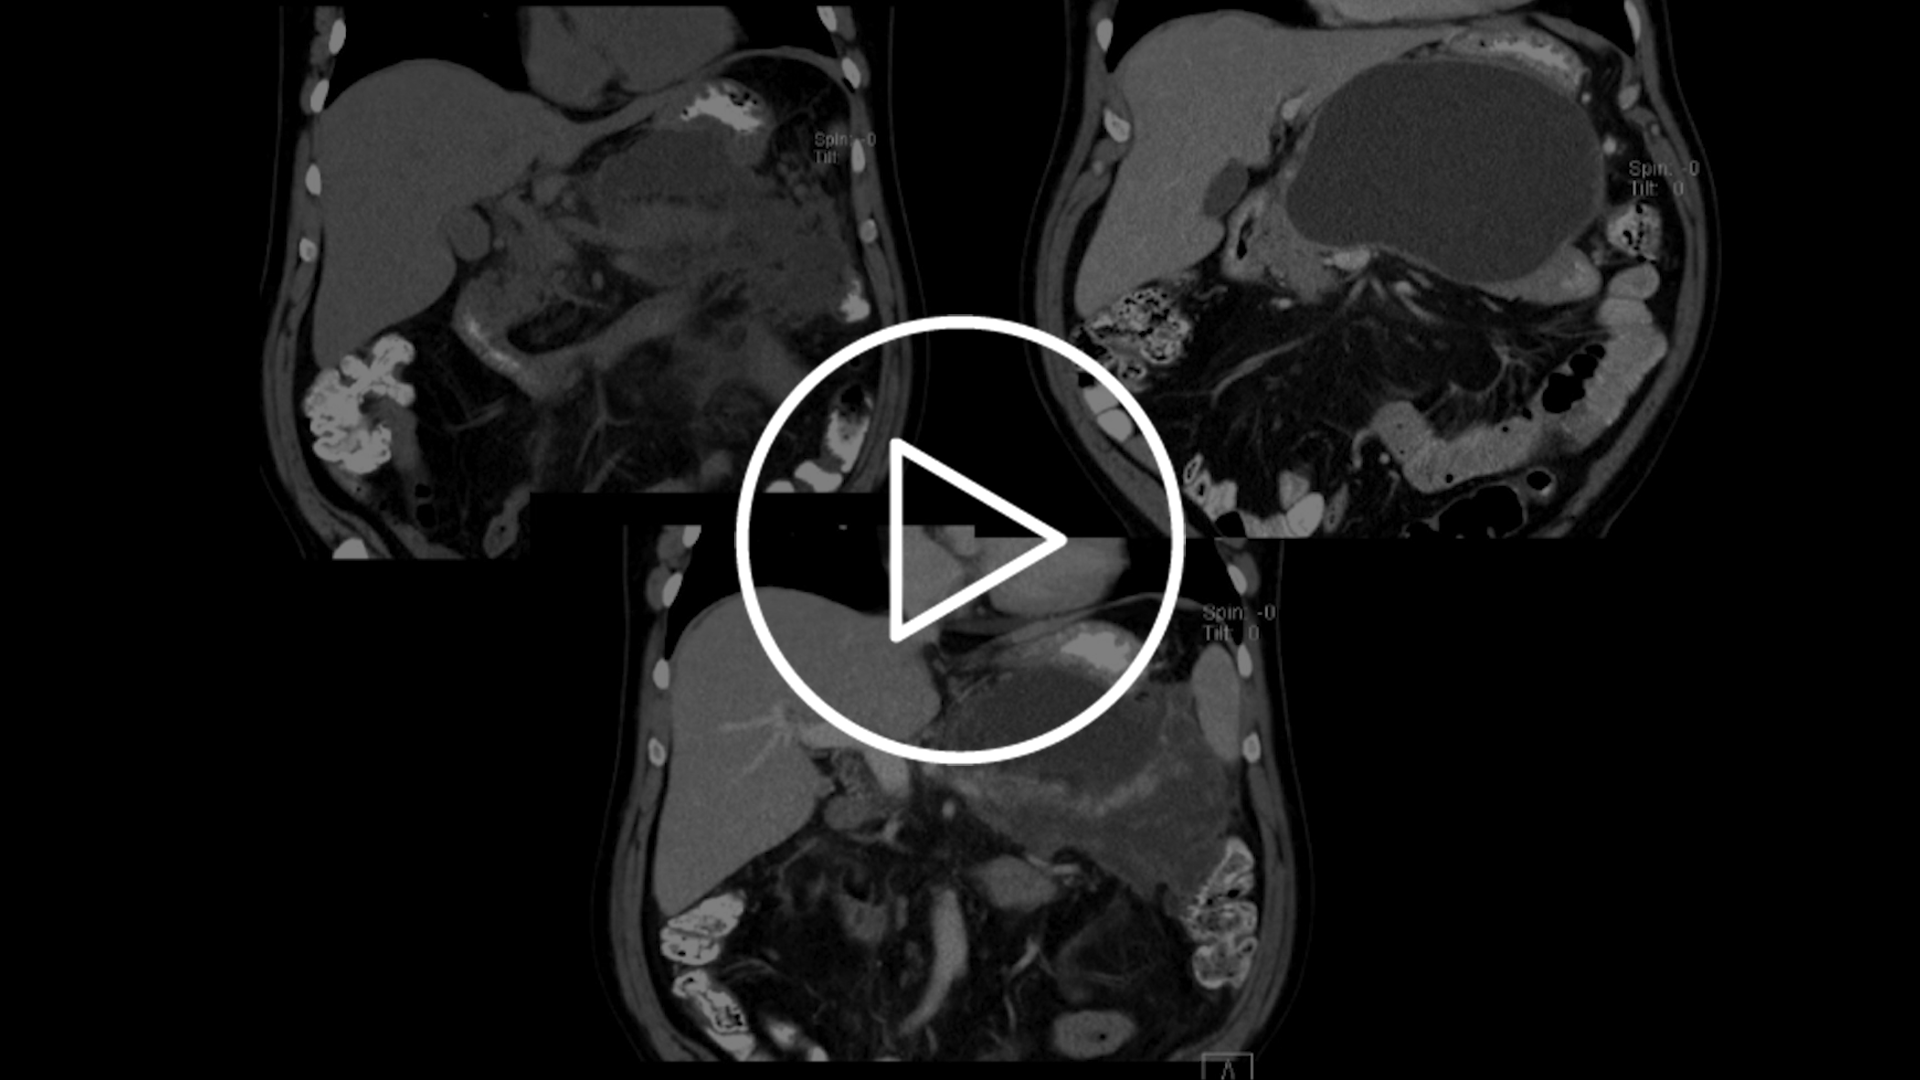

This training is dedicated to experienced Hot AXIOS users. Enhance your expertise with this blended learning program which continues the learning journey by focusing more on gallbladder and bile duct drainage.

You will be enrolled to the 2 e-Learning modules: one focused on gallbladder, the second on bile duct drainage. It should take no more than 60 minutes to complete the modules.

This part of the training includes lecture and hand-on practice. During this session, you will expand your knowledge, gain useful tips and tricks and have the ability to ask our faculty questions.

Continue your learning journey with us. Check our continuing education offering: access the EUS video cases and other educational resources on EDUCARE and contact us for e-Preceptorships and e-Proctorships opportunities, webinars and case support.